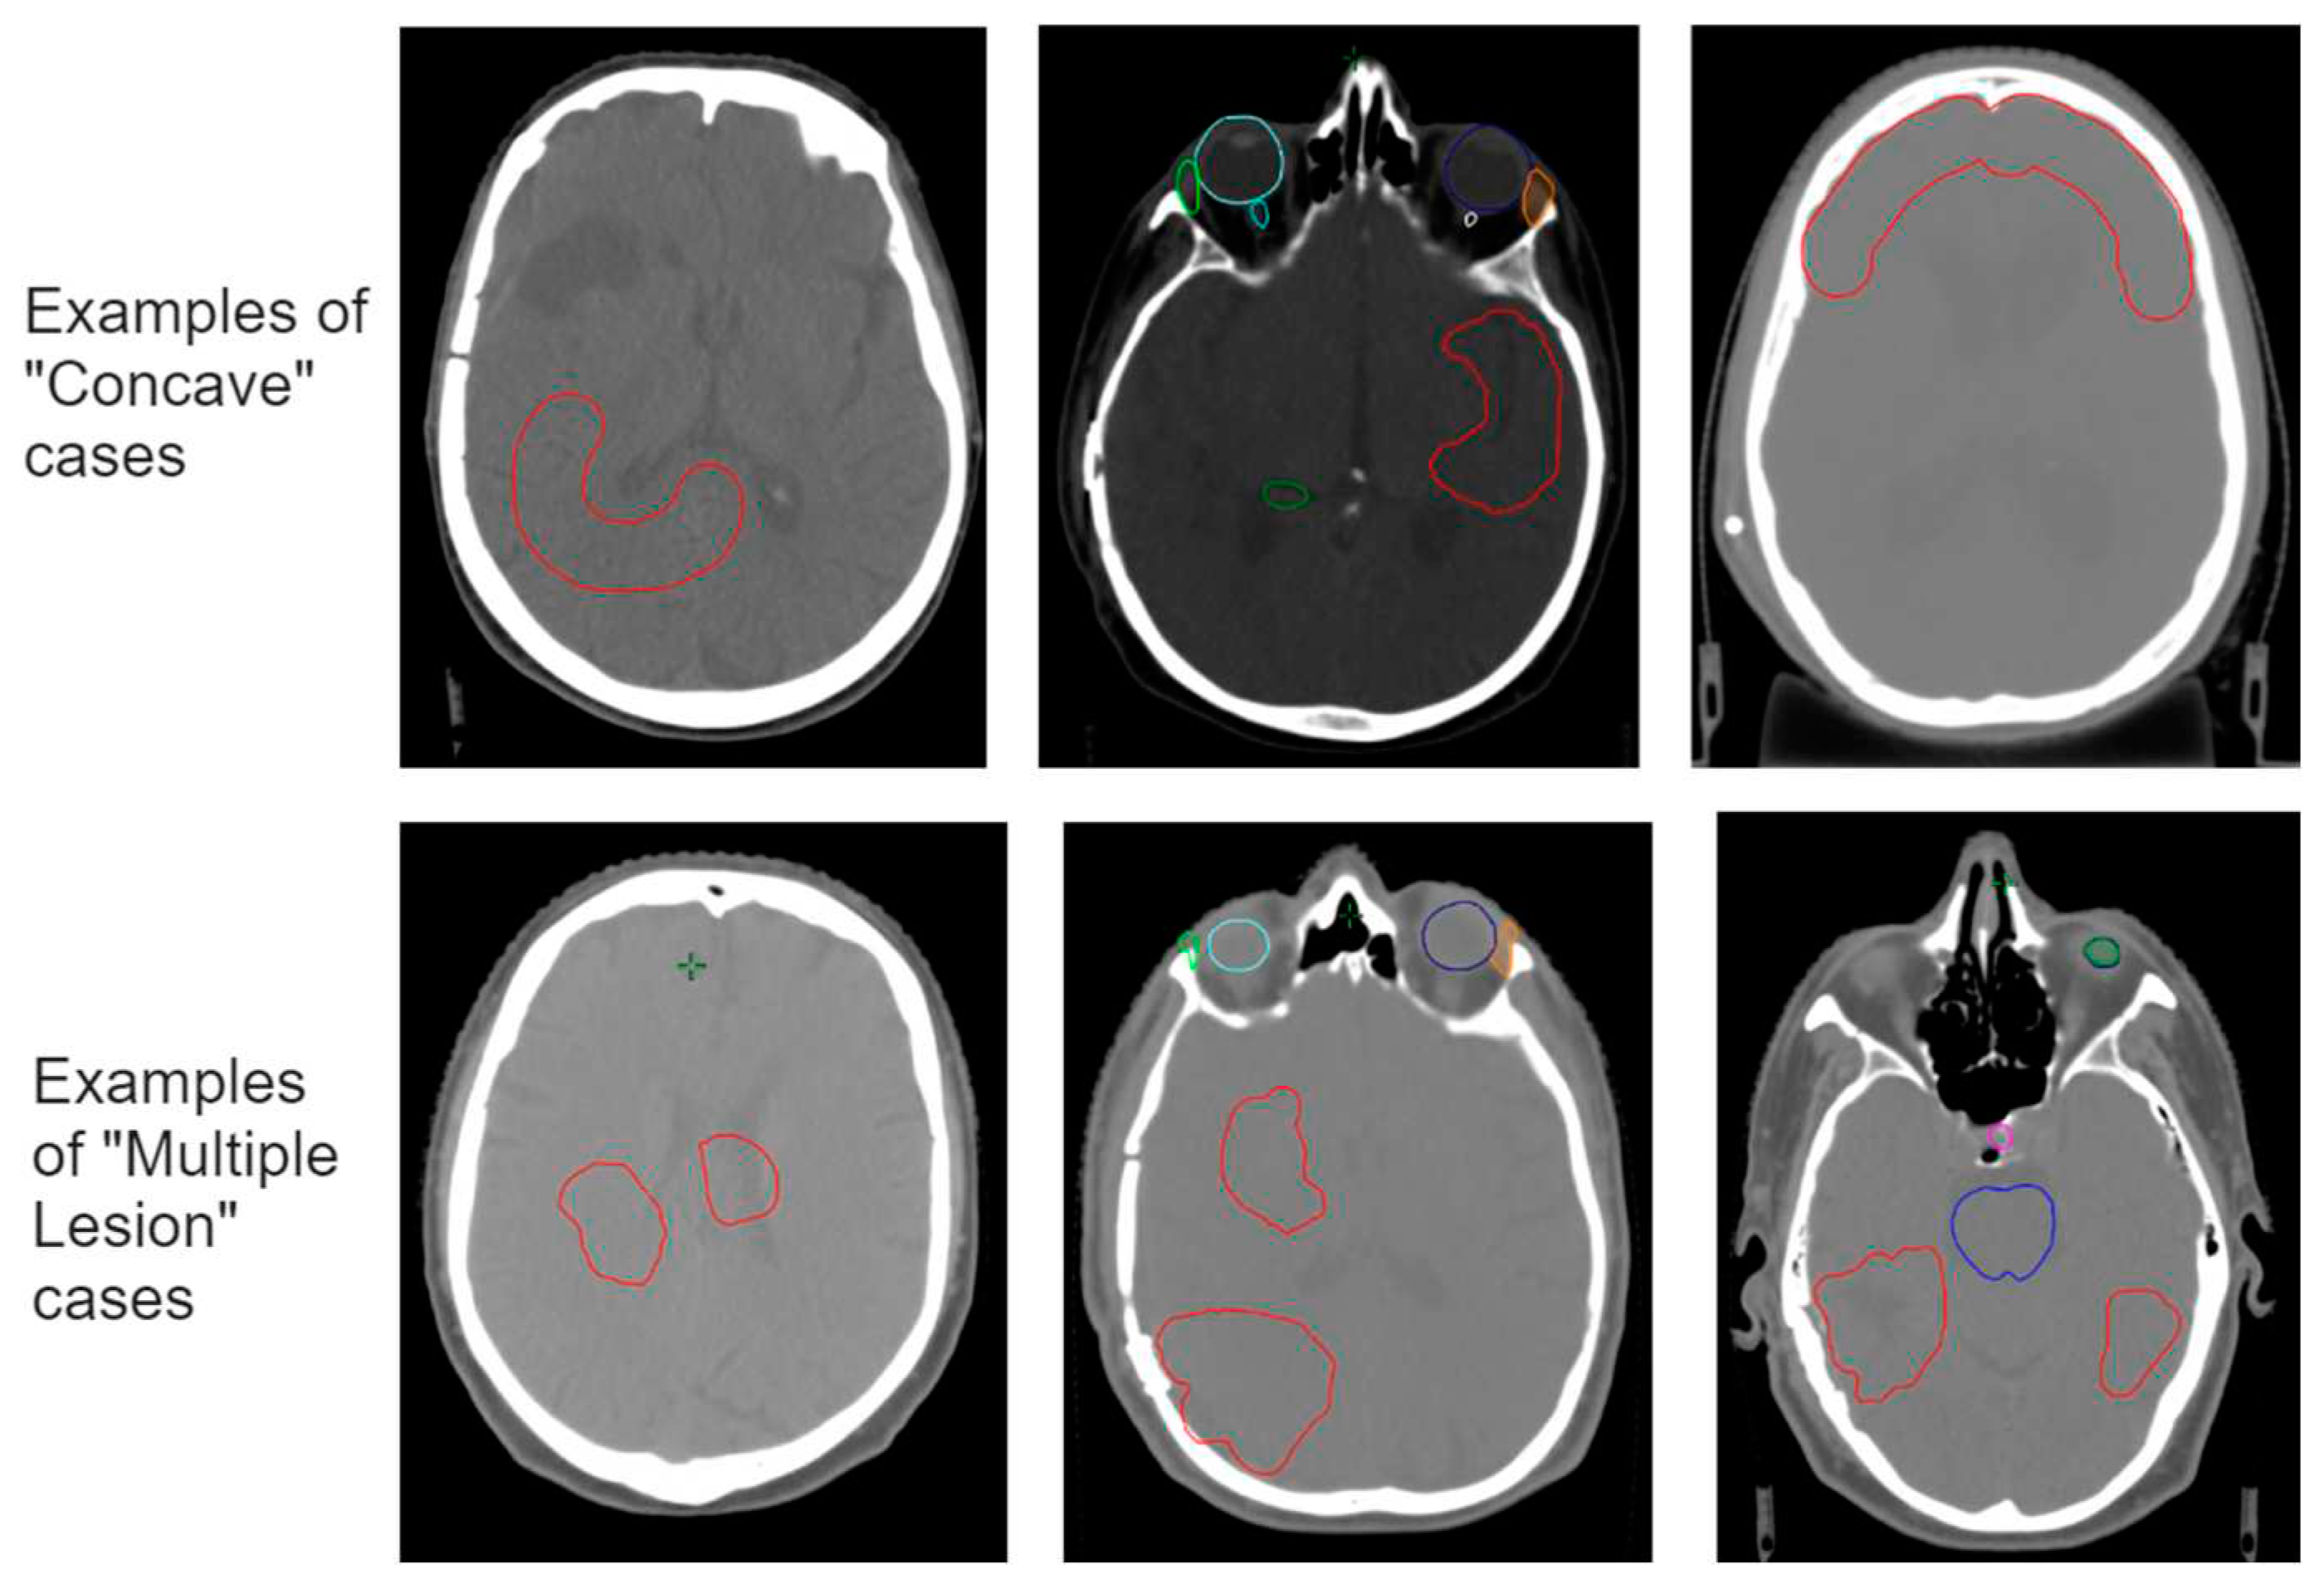

To assess the robustness of the model, and upon first analysis and evaluation of the standard test set of 20 cases, a specific “worst-case” test set was selected of cases where we expect the model to fail or have difficulties. The PTVs of these cases were manually manipulated to simulate rare cases not described by the training dataset (out-of-distribution cases), but also present a challenge in terms of the physical limitations of obtaining perfect dose conformity. Among these 10 cases, we included: (i) targets of larger and smaller size than those present in the training set, (ii) targets consisting of multiple lesions, (iii) irregular shapes such as elongated or concave targets, and (iv) present an overlap between the target and OARs.

According to the “worst case test set” results, we gained insight into which situations the model performs poorly and where it could benefit from additional training. Our observations showed that the prediction model mainly struggled with the physical limitations of conforming the dose according to the targets outlines for specific shapes. Where conformity decreases with concave shapes or multiple targets close to each other, the dose predictor overestimates the dose fall-off in these regions. To increase the overall robustness of the model but specifically to improve the model for these situations, we updated the trained model by including a set of concave-shaped target cases and a set of cases where the target consists of multiple lesions.

The respective new training sets were constructed by means of manually adjusting the target volume (Figure 2). The 10 cases used for both sets are from different patients and have not been used in any previous model training. All new cases received a dose planning according to the same protocol described above, to serve as the reference dose.

Figure 2. Examples of the additional training cases for the concave targets (above) and the multiple targets (below). The targets are drawn manually in red and do not represent actual tumor situations. Structures in other colors represent OARs.